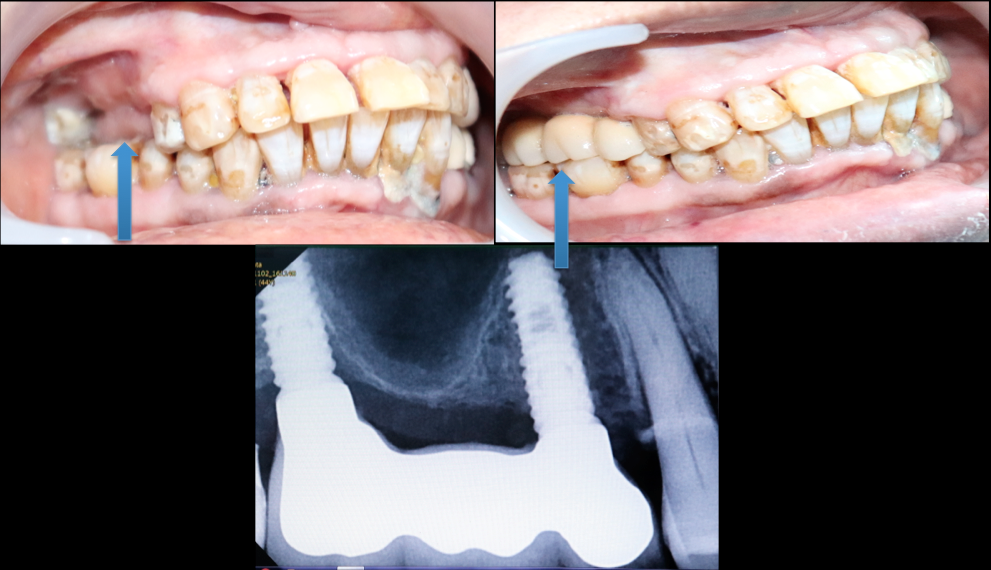

SUCCESSFUL TREATMENT STORIES